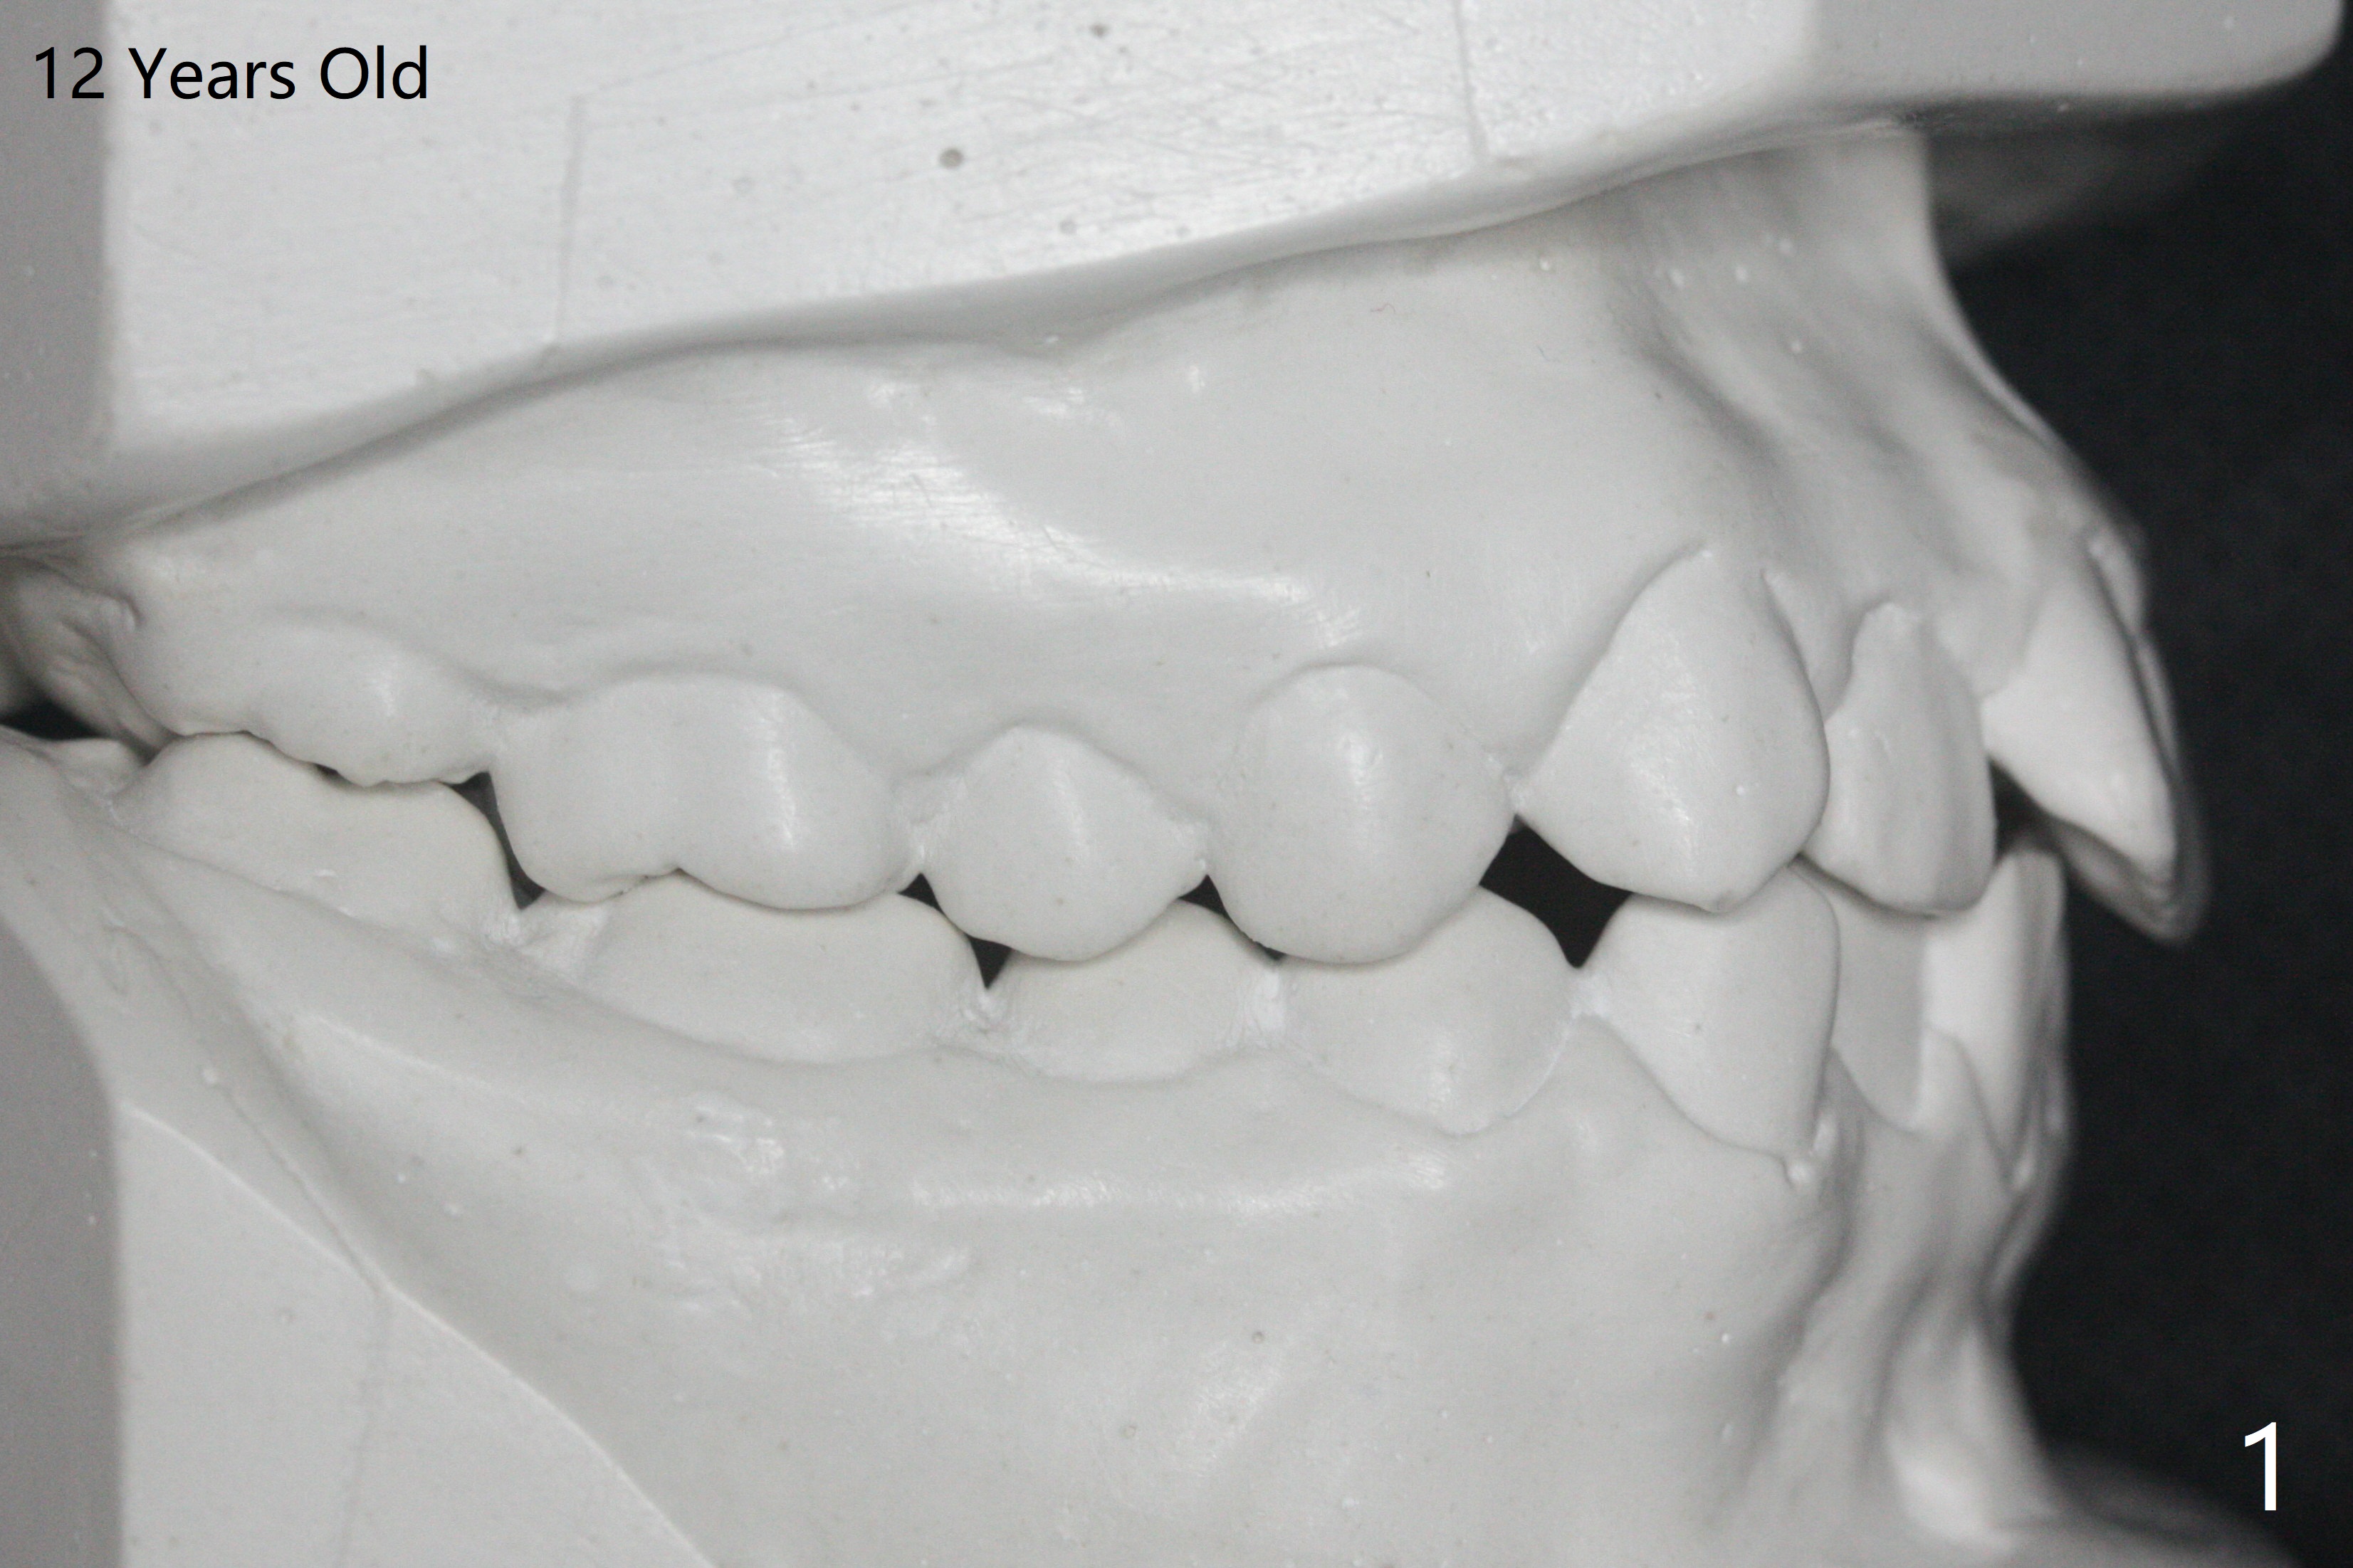

A 12-year-old woman has severe crowding including UL7 impaction (Fig.1-5), finishes non-extraction orthodontics at the age of 15 (Fig.1'-5') and returns for retainer remake at 19 (Fig.1''-5''). Four years post debanding, UL7 (Fig.4') seems to improve its position (Fig.4'').